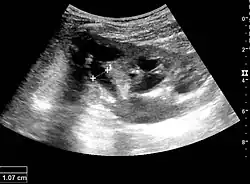

Cortical thickness should be estimated from the base of the pyramid and is generally 7–10 mm. If the pyramids are difficult to differentiate, the parenchymal thickness can be measured instead and should be 15–20 mm (Figure 3). The echogenicity of the cortex decreases with age and is less echogenic than or equal to the liver and spleen at the same depth in individuals older than six months. In neonates and children up to six months of age, the cortex is more echogenic than the liver and spleen when compared at the same depth.[1]

Figure 3. Measures of the kidney. L = length. P = parenchymal thickness. C = cortical thickness.[1]